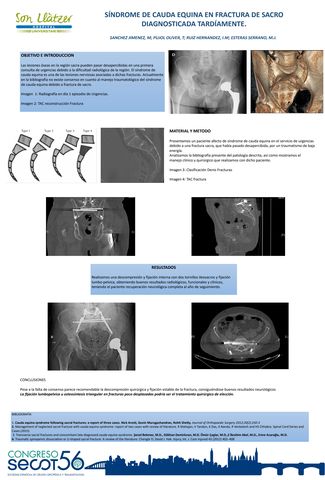

Síndrome de Cauda equina en fractura de sacro diagnosticada tardíamente

Título: Síndrome de Cauda equina en fractura de sacro diagnosticada tardíamente

Autores:

MARCOS SANCHEZ JIMENEZ, TOMÁS PUJOL OLIVER, ISABEL MARÍA RUIZ HERNÁNDEZ, MATÍAS JOSÉ ESTERAS SERRANO

Ver eposter